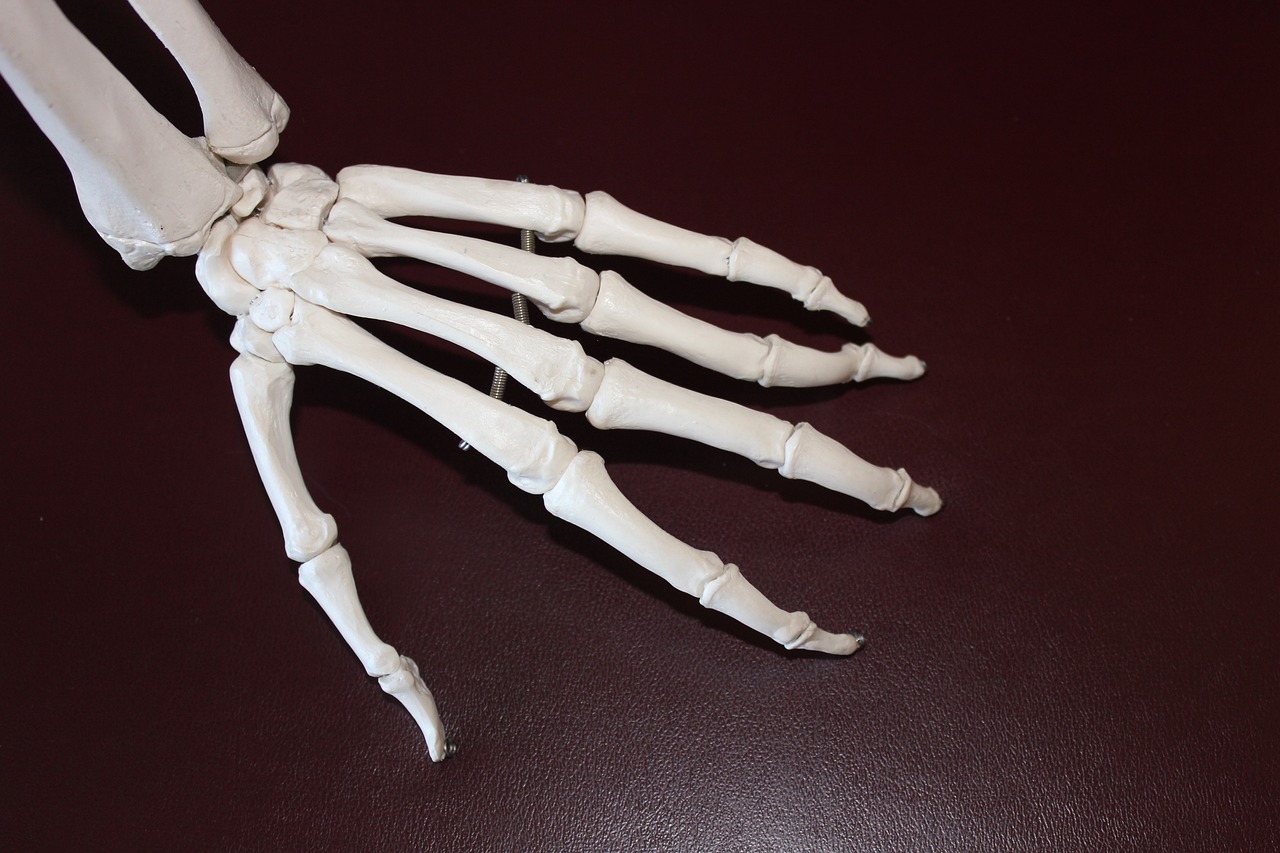

일반적으로 여러 관절에 지속적인 통증과 부종은 류마티스 관절염의 초기 증상의 특징입니다. 그리고 관절을 만지면 열감이 느껴지는 경우가 많습니다. 일반적으로 영향을 받는 관절에는 손, 손목, 무릎, 발이 포함됩니다.

시간이 지남에 따라 류마티스 관절염은 특히 손과 손가락의 관절 기형으로 이어질 수 있습니다. 여기에는 백조목 변형이나 부토니에르 변형(단추구멍 변형)이 포함될 수 있습니다.

관절 기형은 손 기능에 영향을 미칠 수 있습니다.